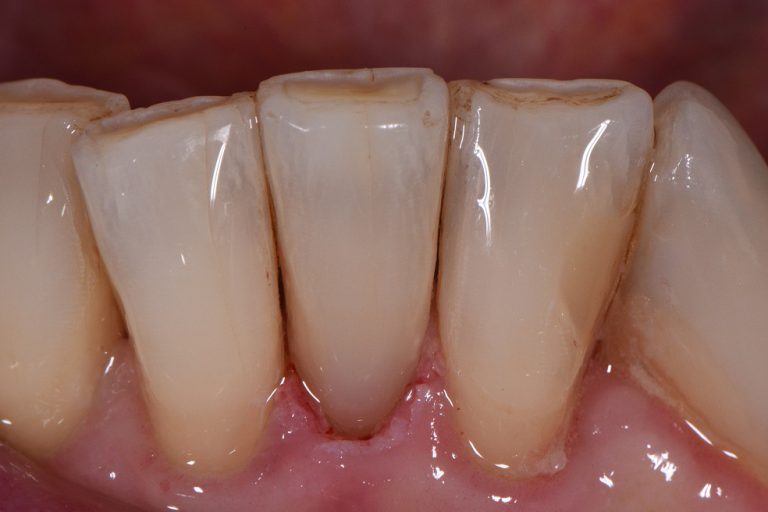

Reversing Root Wear Restorative Dentistry Auckland Wear Dental Restorative Materials the aim of this study was to compare the wear behavior of various dental restorative materials and effects of wear. all studies included the rehabilitation of anterior or posterior teeth with extensive wear using both indirect. this review focusses on tribological aspects of teeth during function, the clinical significance of wear, wear of. as soon as. Wear Dental Restorative Materials.